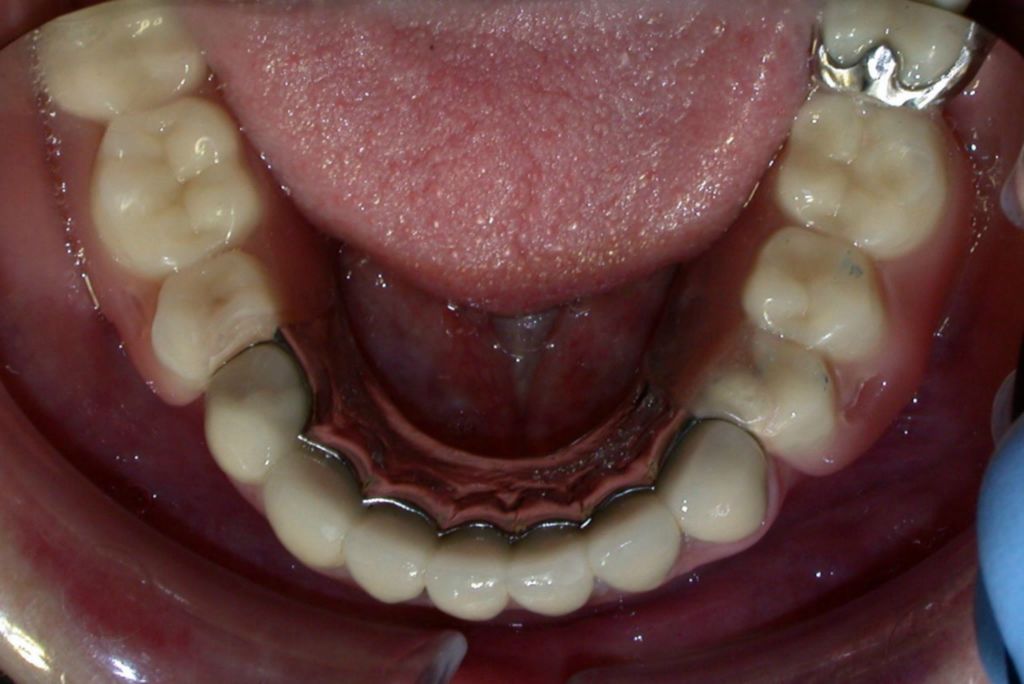

Partial denture with precision attachments